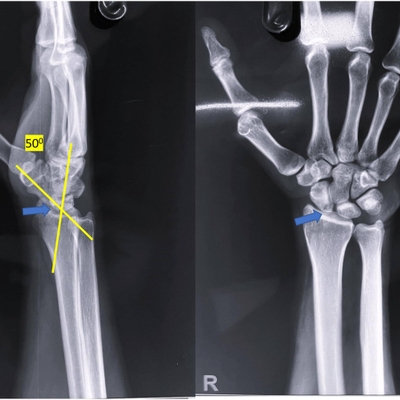

Click on an image below to view more info.